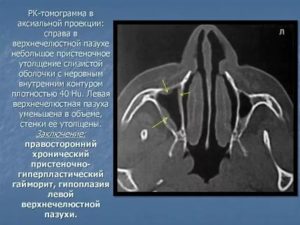

Гиперплазию эпителия можно заметить только на рентгеновских снимках. При подозрении на утолщение врач выдает направление на рентген, который позволит заметить даже минимальное увеличение эпителиального слоя в виде затемнения. Рентген также показывает наличие и уровень жидкости в синусах, а по ее расположению можно определить степень воспаления.

Для дополнительной диагностики используют МРТ и КТ. Применяя метод компьютерной томографии, ЛОР-врач может оценить размеры разрастания, а также проходимость протоков.

Для постановления диагноза используют риноскопию, в ходе которой специалист может обнаружить отечность слизистых оболочек, бледность определенных участков, повреждение сосудов. Если присутствуют симптомы, характерные для хронического гайморита, необходим рентген носовых пазух. Только на рентгеновских снимках можно заметить начальные стадии образований и пристеночный отек.